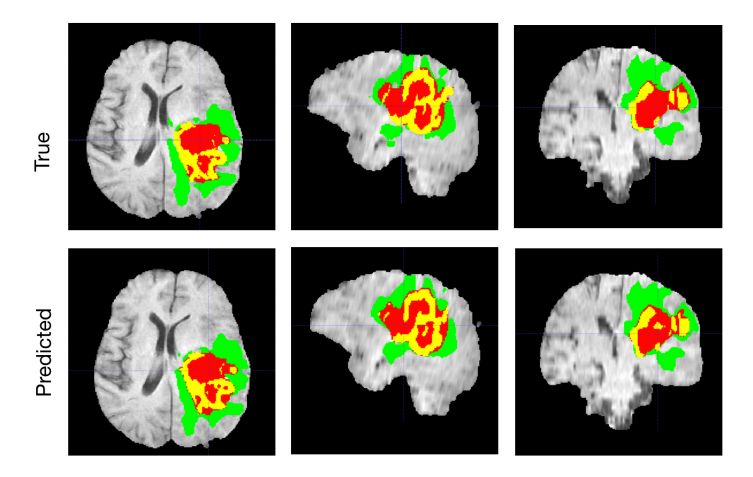

脑肿瘤语义分割:

- 自动检测:深度学习模型能够从CT、MRI、X光等医学影像中自动检测和识别疾病。例如,模型可以检测肺结节、乳腺肿块、脑肿瘤等病变。

- 分类:通过分析影像,深度学习可以将病变分类为不同类型,帮助医生做出准确的诊断。

- 区域分割:深度学习可以精确分割医学影像中的不同结构,如肿瘤区域与正常组织的边界。这对于治疗规划和术后评估非常重要。